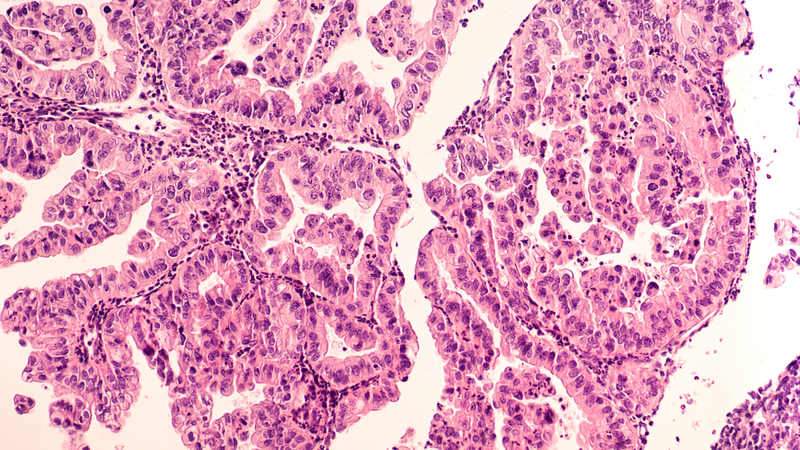

Ovarian cancer begins in the ovary or the fallopian tube. It is often difficult to detect in the early stages. The cancer quickly develops resistance to chemotherapy and is usually fatal.

To validate their initial findings, the researchers studied tissues collected from more than 200 patients from the University of Chicago. They found no CT45 at all in 82 of those patient samples, but they found high levels in 42 patients, all of whom had much longer disease-free survival.

A larger study, using sequence data from The Cancer Genome Atlas, confirmed their initial results, leading to their conclusion that “CT45 expression is a novel prognostic indicator for advanced-stage, high-grade serous ovarian cancer.”